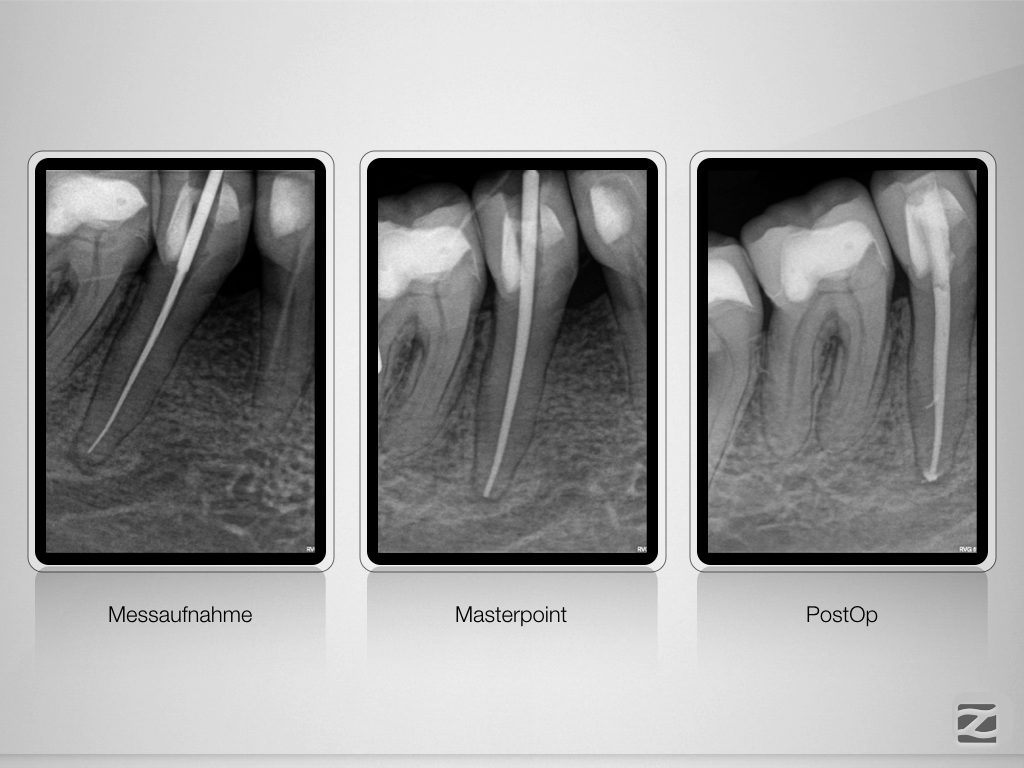

45D.008

Fährtensuche